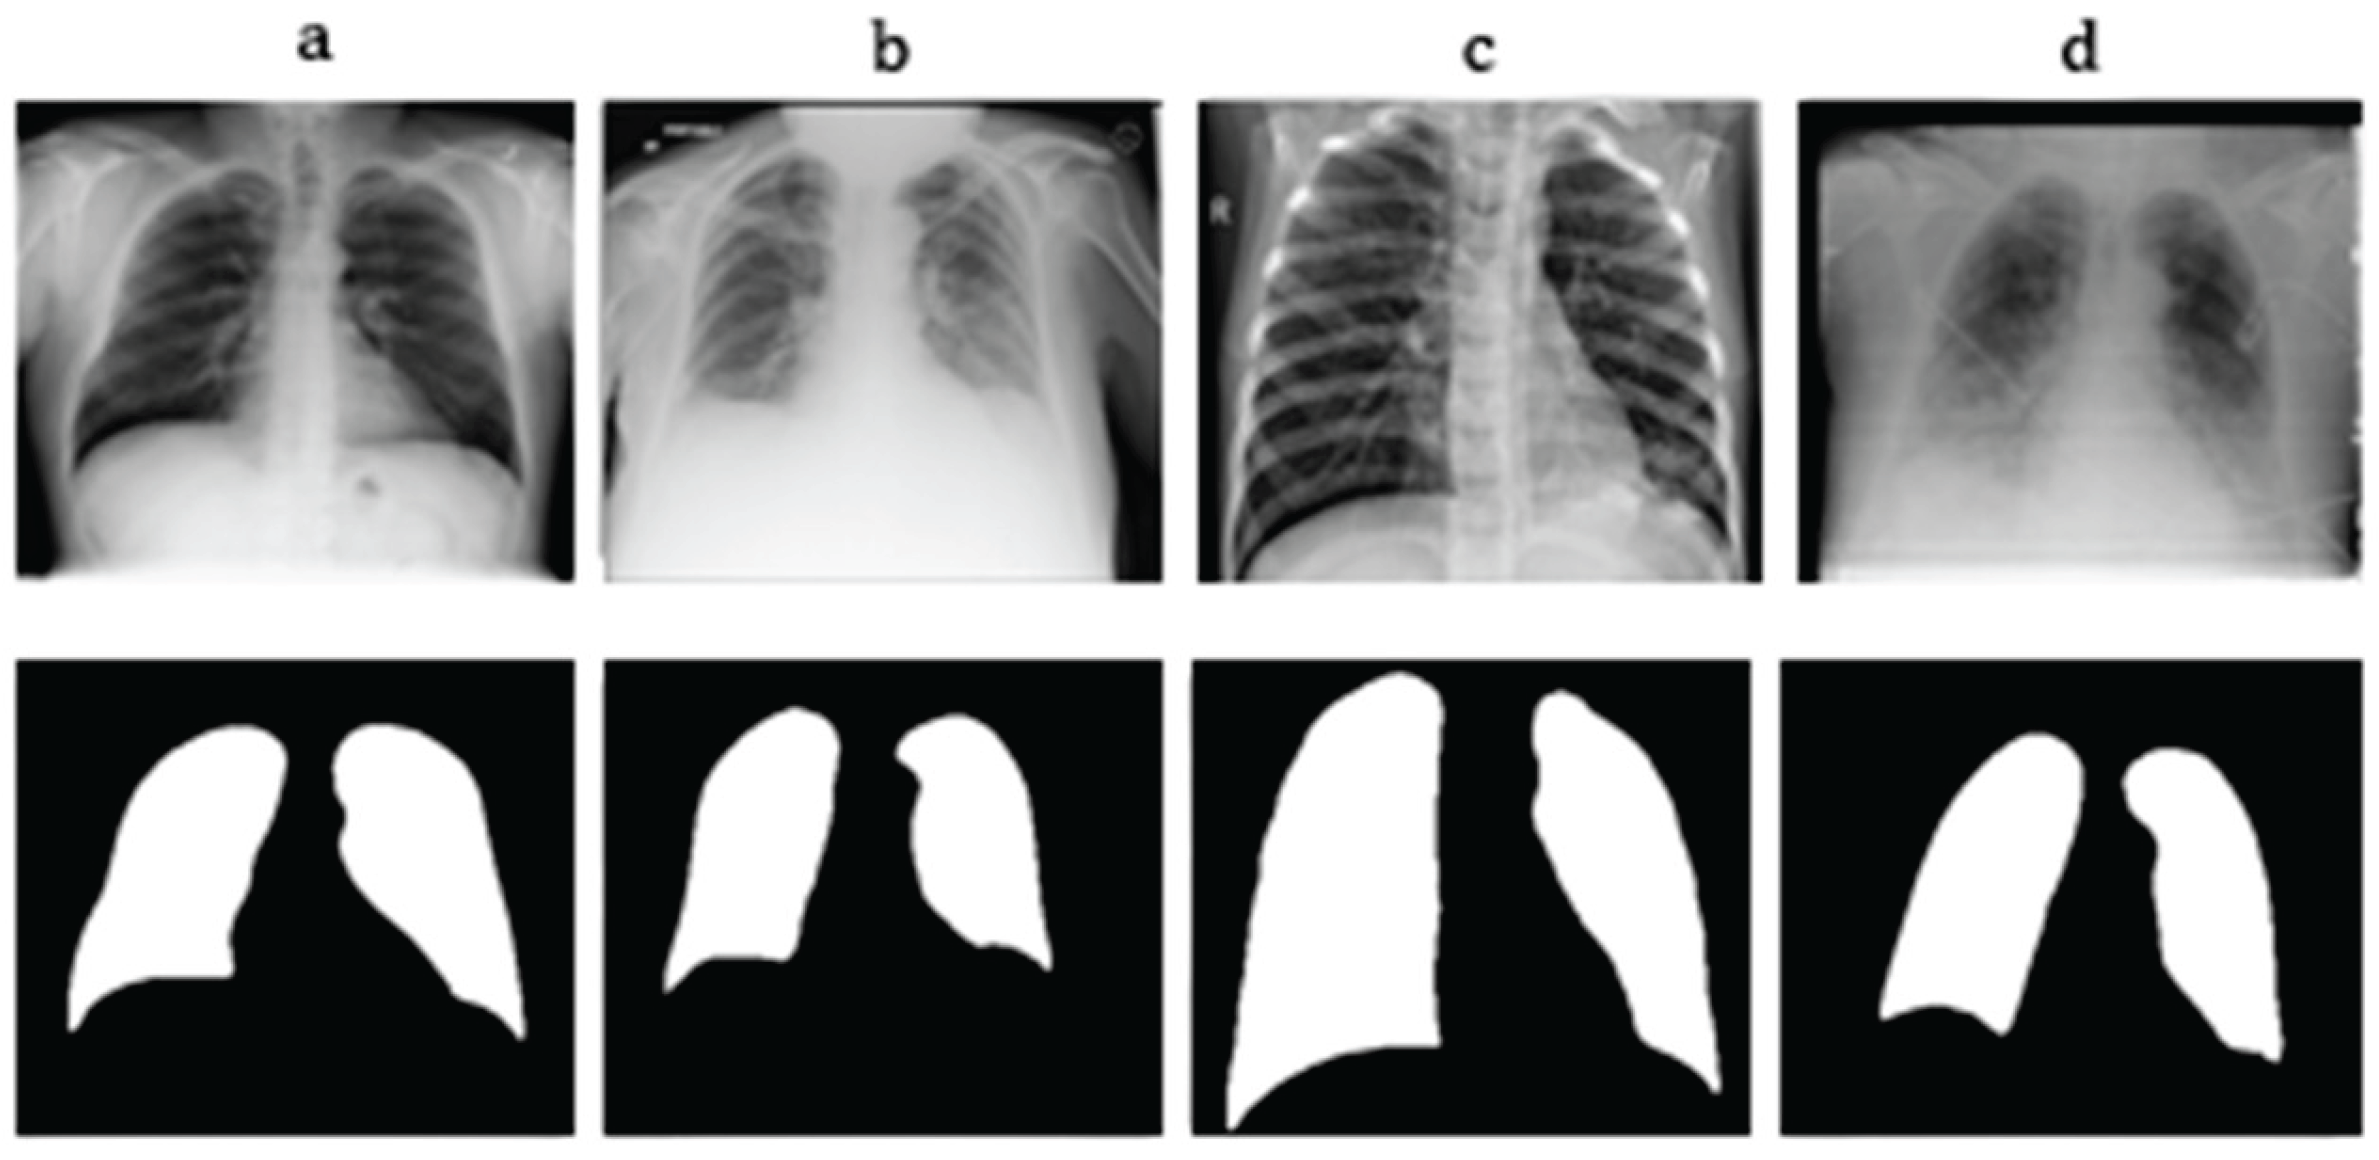

3.1.1. Pulmonary Region of Interest (ROI) Extraction

- Lung Region Isolation

- Segmentation Phase: Otsu’s Thresholding

- Binary Mask Result:where denotes the image intensity at pixel location .

- Geometric Phase: Connected Components

- Assuming the lungs correspond to the two largest contiguous dark regions, the mask was filtered by retaining the two largest components:

- Validation Phase: Area Fraction Heuristic

- Decision Rule